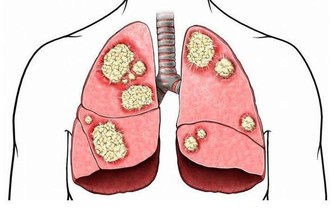

肺是人體極其重要的呼吸器官,是體內氧氣循環的關鍵。不過,現代很多人存在不良的生活和飲食習慣,比方說,時不時抽煙喝酒,動不動就熬夜……導致肺部功能或多或少受損,影響身體健康。那麼,肺好不好,可以通過哪些方法判斷?冬季養肺應該怎麼做?

肺好不好,不妨看看5個地方